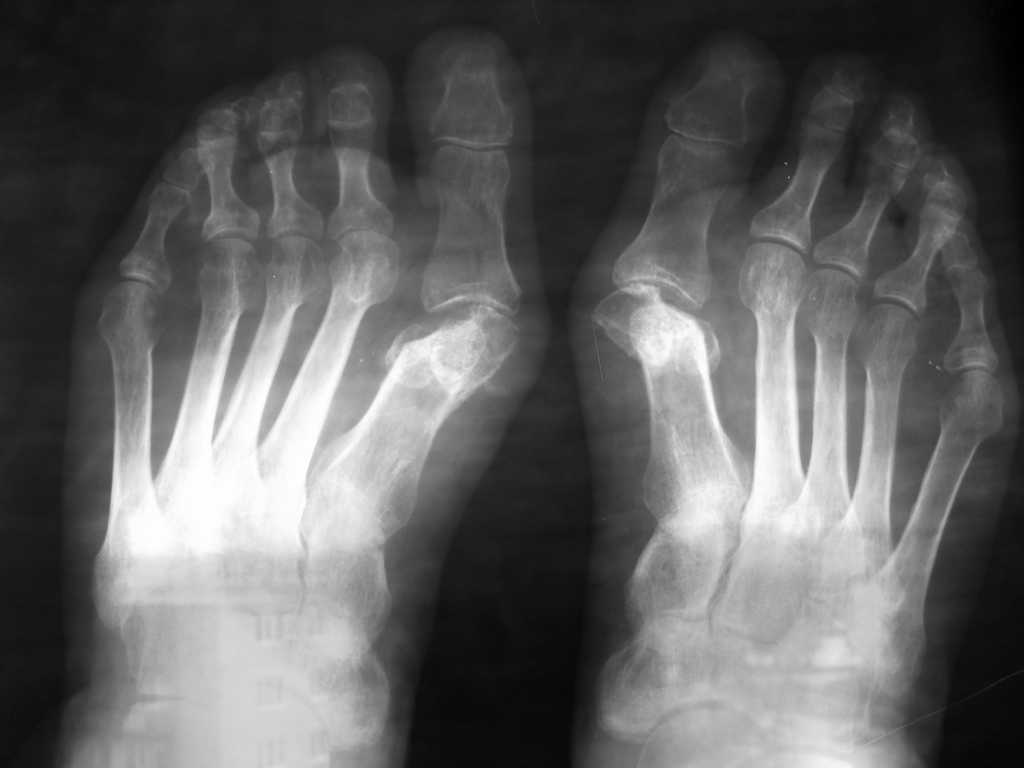

Уважаемые коллеги. Помогите определиться с дальнейшей тактикой лечения. У пациентки после операции по поводу вальгусной деформации 1-х пальцев стоп, выполненной в одной из клиник нашего города 8 месяцев назад имеется картина асептического некроза головок 1-х плюсневых костей. Беспокоят боли в плюсне-фаланговых суставах, больше на правой ноге. (По-видимому, была выполнена операция Шаде-Бома с клиновидной резекцией головок 1-х плюсневых костей). Помогите советом. Мы думаем выполнить моделирующую резекцию головок плюсневых костей, удалить экзостозы, сформировать по возможности сферическую форму головок. Либо напрвить больную на эндопртезирование плюсне-фаланговых суставов.

об асептическом некрозе головк плюсневых костей, на самом деле, говорить рано. На сей момент имеет место неконгруэнтоность в первых плюснефаланговых суставах, которое надо устронять. Об эндопротезировании в данном случае говорить не приходится, весьма не пригодное состояние костной ткани для данного вида вмешательства. Я бы предпринял на первых плюсневых костях ревизионную СКАРФ остеотомию с восстановлением конгруэнтности в первых плюснефаланговых суставах и одновреенным выполнением латериального релиза для восстановления мягкотканного баланса.

Далее (не понятно какая правая а какая левая стопа-нет маркировки)на левой стопе наобходимо вмешательство на втором, третьем и четвертом лучах - имеет место крючкообразная деформция пальцев и к тому же на помешало бы некоторое укорочение длины перечисленных плюсневых костей , так как длина первой плюсневой кости неадекватно мала.

Уважаемый Сергей! При взгляде на представленные рентгенограммы не сложилось впечатления об асепт. некрозе головок первых плюсневых костей. Узнать о целях и технике выполненного вмешательства, видимо, не удастся. Не достаточно данных Вашего осмотра, есть ли натоптыши под головками остальных плюсневых костей, каких? Степень смещаемости первого луча? Судя по положению сессамовидных костей, есть надежда на восстановление отношений в первом ПФС, после остеотомий Скарфа, Людлофа или Лапидуса (либо -либо) с фиксацией винтами Герберта или Бароука. Дополнил бы аддуктотомией (2 м/п промеж) и операцией Мак-Брейта. При "натоптышах" под головками 2-3-4- пл. костей использовал бы разгружающие чрезшеечные остеотомии по Вейлу ( на 5-й пл.-медиализирующую остеотомию ее диафиза), с фиксацией аналогичными винтами (разной длины). Избыточную мобильность пяточной кости в подтаранном суставе при вальгусном ее положении (если в вашем случае это присутствует) я корректирую постановкой кейджа в тарзальный синус. Опыт эндопротезирования имею только с использованием Moje-implants, в данном случае считаю ЭП - возможным, конкретно под тип протеза и + с использованием костной пластики.